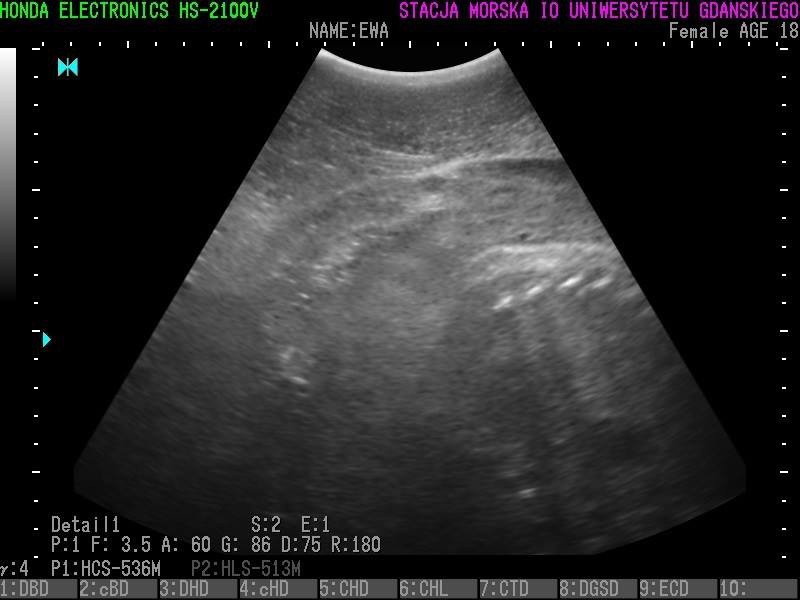

Wszystkie helskie foki - czyli Agata, Ewa, Unda Marina i Ania - są w ciąży. To wyniki badań ultrasonograficznych, które przeprowadzono w miniony piątek (23 grudnia).

• Z radością więc informujemy, że tego roku wszystkie nasze cztery samice spodziewają się potomstwa - czytamy na profilu Fokarium.

Szczenięta urodzą się najprawdopodobniej w marcu 2017 roku.